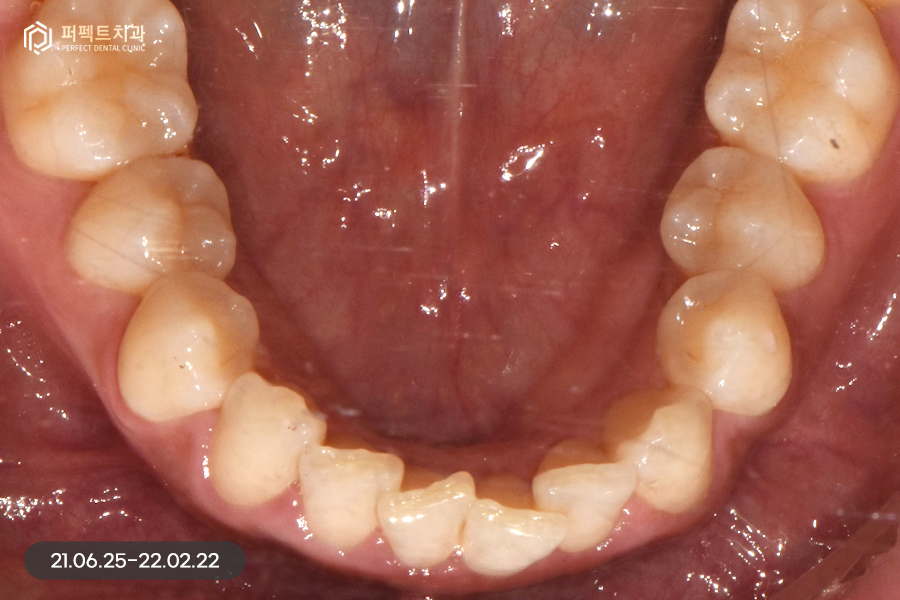

사진으로 보았을 때 큰 문제가 없어보이지만 실제로는 위 아래 치열이 삐뚤빼뚤하고 아래 치아의 경우 위 치아보다 더 틀어짐이 심했는데요. 그렇기 때문에 부분교정을 5개월 정도 진행하였습니다.

교정 후 치아가 가지런하게 펴졌는데, 교정을 하면 항상 생기는 문제점 중 하나가 바로 고르지 못한 치아들이 가지런하게 펴지면서 잇몸 사이 공간인 블랙트라이앵글입니다.

위 환자분도 마찬가지로 블랙트라이앵글이 발생했고, 이 공간을 해결함과 동시에 치아 색상도 하얗게 변화를 주길 원하셨습니다. 그렇기 때문에 위, 아래 6개 치아를 라미네이트 진행하였습니다.